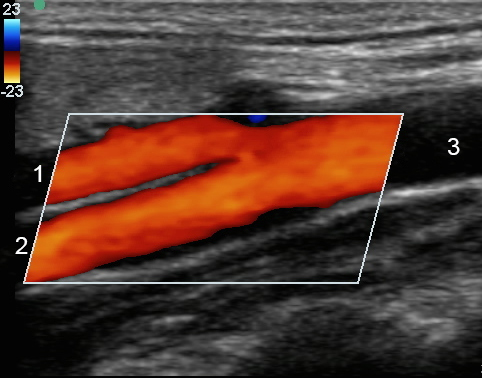

Bifurcación carotídea con color

1. Arteria carótida externa (ACE)

2. Arteria carótida interna (ACI)

3. Arteria carótida primitiva